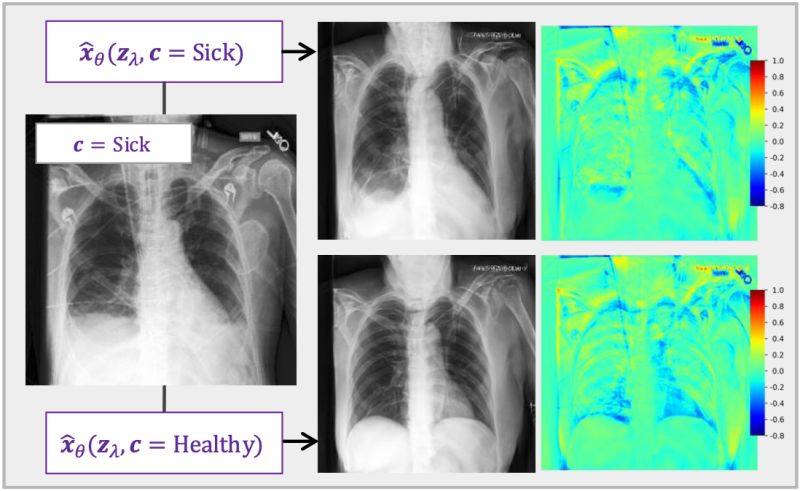

- Conditional Diffusion Models as Medical Image Classifiers

- GitHub - faverogian/med-diffusion-classifier: Official implementation ...